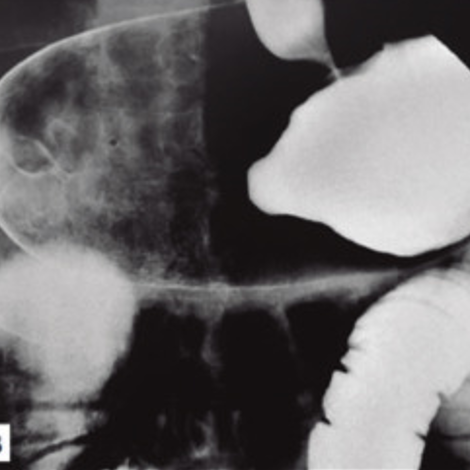

Una gammagrafía ósea es una prueba de diagnóstico por imágenes de medicina nuclear que ayuda a diagnosticar y controlar varios tipos de enfermedades óseas. El médico puede solicitarte una gammagrafía ósea si tienes dolor óseo inexplicable, una infección ósea o una lesión ósea que no puede verse en una radiografía estándar.

Una gammagrafía ósea también puede ser una herramienta importante para detectar el cáncer que se ha esparcido (metastatizado) al hueso desde la ubicación original del tumor, como la mama o la próstata.

Una gammagrafía ósea implica inyectar una cantidad muy pequeña de material radiactivo (marcador) dentro de una vena. La sustancia viaja a través de la sangre hasta los huesos y órganos. A medida que esta va desapareciendo, emite un poco de radiación. Esta es detectada por una cámara que lentamente escanea el cuerpo.